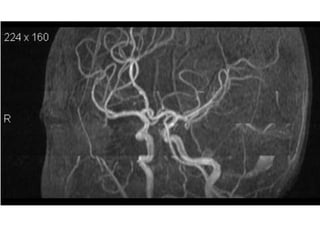

Arteries of the brain (lateral view) - MRA

1. Anterior cerebral artery

2. Anterior communicating artery

3. Basilar artery

4. branches (in insula) of middle cerebral artery

5. Cavernous portion of internal carotid artery

6. Cervical portion of internal carotid artery

7. Genu of middle cerebral artery

8. Intracranial (supraclinoid) internal carotid artery

9. Middle cerebral artery

10. Ophthalmic artery

11. Petrous portion of internal carotid artery

12. Posterior cerebral artery

13. Posterior cerebral artery in ambient cistern

14. posterior cerebral artery in interpeduncular

cistern

15. Posterior communicating artery

16. Posterior inf cerebellar artery.

17. Quadrigeminal portion of posterior cerebral

artery

18. Superior cerebellar artery

19. Vertebral artery